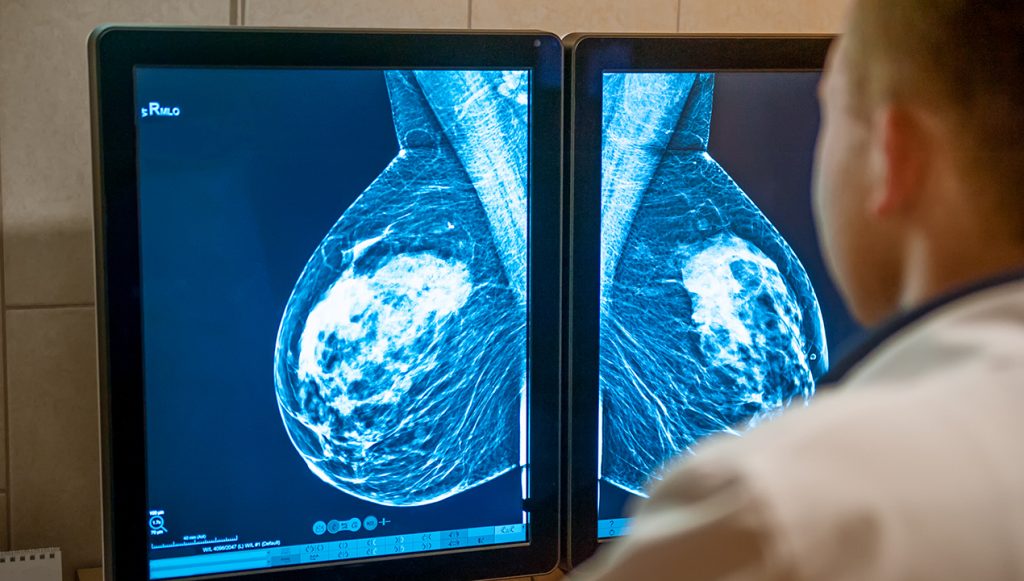

Survival rates for female breast cancer have improved significantly. In the mid-1970s, it was 75%, but for those diagnosed between 2011 and 2017, it reached an impressive 90%. This progress is due to better early detection and effective hormonal treatments. Mammography screenings have also played a big role in this progress.

It’s worth noting that when breast cancer is detected at stage I, the 5-year relative survival rate nearly reaches 100%. However, the outlook becomes significantly more challenging for those diagnosed at stage IV, with the survival rate dropping to 28%.

Mammography, a well-established tool in the battle against breast cancer, is also endorsed by around 19.4% of the surveyed oncologists. Routine mammograms play a crucial role in the early detection, empowering individuals to address potential concerns before they progress to more advanced and challenging stages of cancer.

This screening method also serves as a preventive measure against breast cancer recurrence, offering relief and making a breast cancer patient journey less arduous.